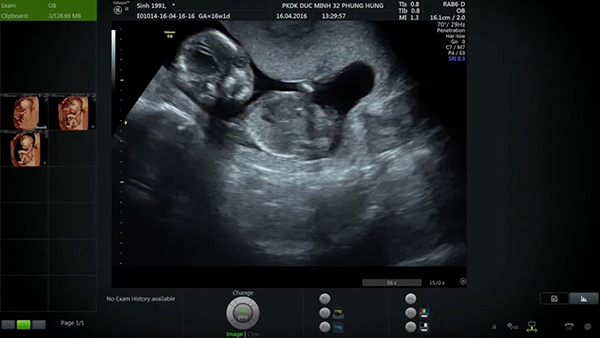

Kích thước thai 16 tuần tiêu chuẩn là khối lượng tầm 100g (3,5 ounce) và dài khoảng 11,5cm (4,5 inch). Trong quá trình siêu âm mẹ có thể nhìn thấy tứ chi của bé đã bắt đầu cử động, tuy nhiên, nó còn quá nhỏ nên mẹ không thể nào cảm nhận được.

+ Sử dụng kĩ thuật siêu âm 4D để tầm soát dị tật thai nhi, kiểm soát cân nặng của mẹ để có đánh giá chính xác nhất về quá trình phát triển của bé